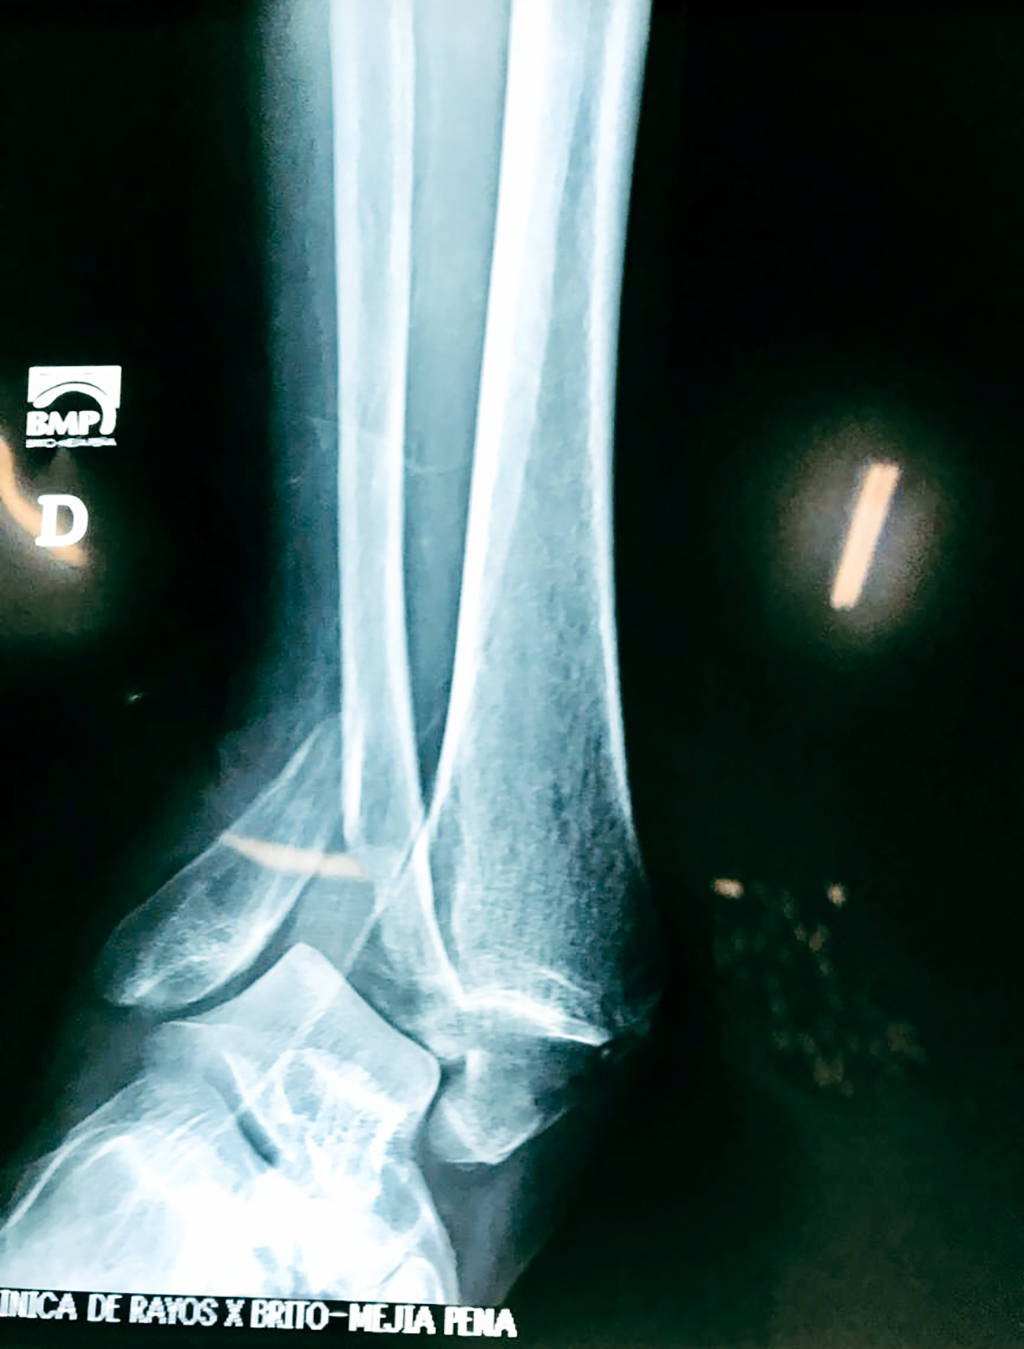

Una fractura de tobillo es la rotura de uno o más de los huesos del tobillo. Estas fracturas pueden ser:

- Los extremos de los huesos están desalineados entre sí (desplazados).

- Los tendones o ligamentos (tejidos que sujetan los músculos y los huesos entre sí) están rotos.

Cuando se necesita cirugía, es probable que esta implique el uso de clavijas de metal, tornillos o placas para sostener los huesos en su lugar mientras la fractura se consolida. Los elementos de soporte pueden ser temporales o permanentes.